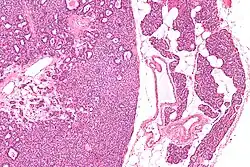

Micrograph of a parathyroid adenoma (left) and normal parathyroid gland (right). H&E stain.